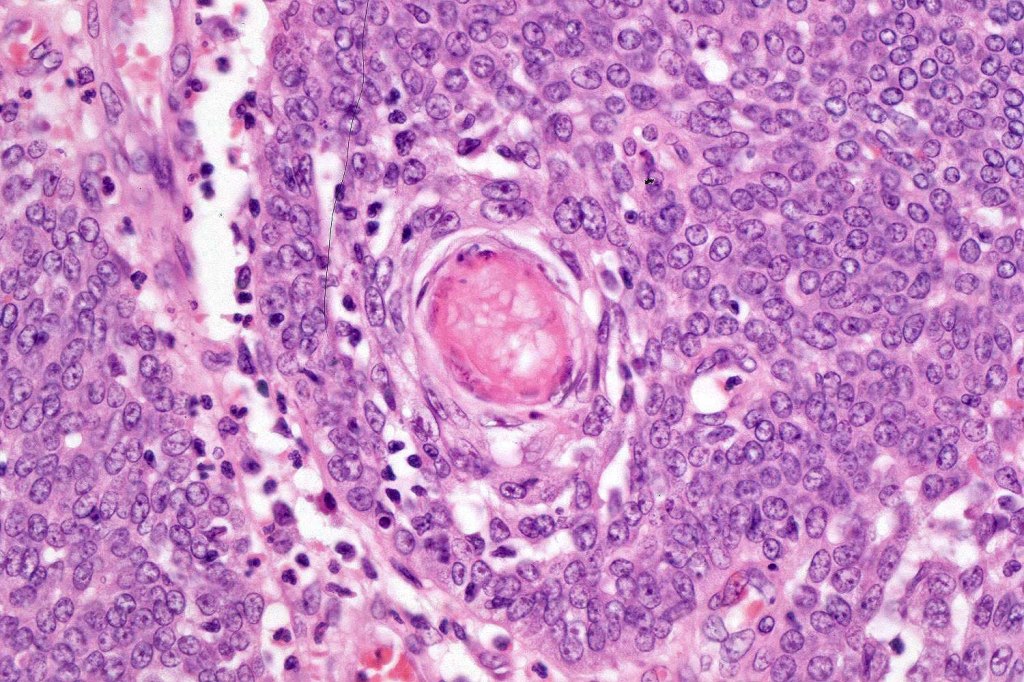

Histological features

•Tumors are composed of an admixture of darkly staining basaloid cells with hyperchromatic or vesicular nuclei and more obvious sebaceous cells with eosinophilic, bubbly, multivacuolated cytoplasm frequently indenting the nucleus (scalloped)

•Variable Lymphovascular invasion & perineural infiltration

•Focal squamous differentiation with keratinization can be present resulting in confusion with squamous cell carcinoma

Sebaceous carcinoma from a patient with Muir-Torre syndrome kindly shared by Dr. Antonina Kalmykova.